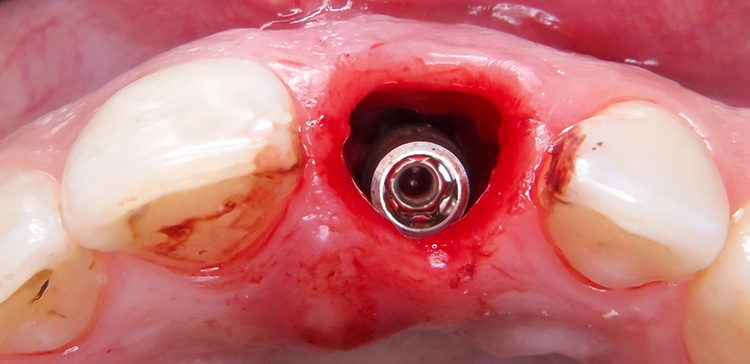

Chirurgischer Eingriff: Extraktion und Insertion

Unter Lokalanästhesie wurde der beherdete Zahn 21 extrahiert und hierbei auf die maximale Schonung der vestibulären Lamelle geachtet. Die Entzündung konnte rückstandslos entfernt werden. Die Sondierung ergab eine intakte faziale Knochenlamelle (Abb. 6). Die frische Extraktionsalveole wurde als Implantatbett aufbereitet und das Implantat (BLX ø 4 mm, 14 mm) entsprechend der Planung dreidimensional im palatinalen Bereich der Alveole inseriert [3,6] (Abb. 7 und 8).

Kapogianni

Das BLX-Implantat hat einige Besonderheiten im Design. So nimmt beispielsweise das Gewinde des Implantats zum krestalen Bereich hin an Stärke zu, sodass zusätzlich zur horizontalen Kondensation auch vertikal Knochen kondensiert wird. Ziel ist eine Primärstabilität im gesamten Implantatbett basierend auf einer homogenen Krafteinleitung. Drucknekrosen sollen so verhindert werden. Im krestalen Bereich ist das Implantat um 1/10 reduziert, um das sensible Gewebe in der Kortikalis drucklos zu lassen. Das BLX-Implantat konnte mit einer für die Sofortversorgung ausreichenden Primärstabilität (mind. 45 N/cm2) inseriert werden.